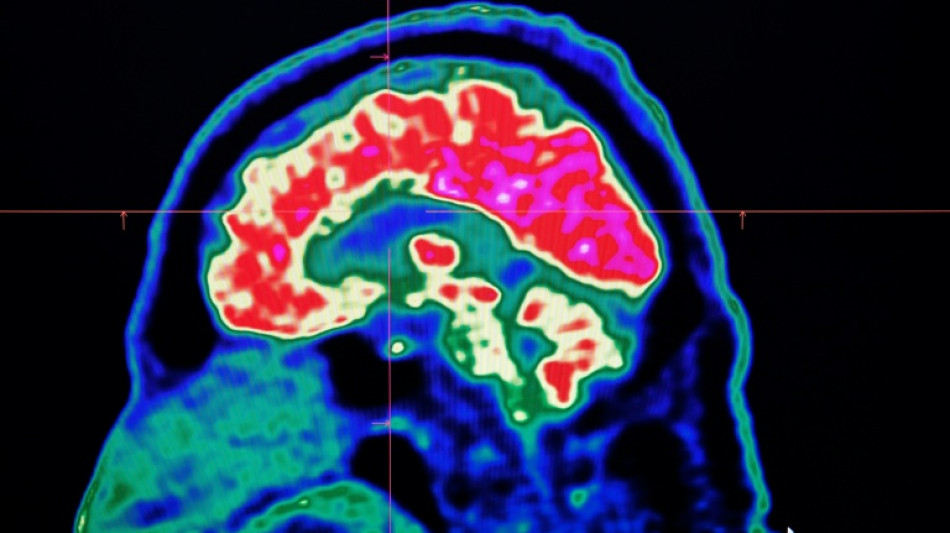

Final report casts doubt on existence of Canada mystery brain illness

A Canadian medical report published Friday found no evidence linking environmental factors to an unusual set of neurological symptoms affecting hundreds of people, a five-year saga that has shaken a small Atlantic province.

In 2021, health officials in New Brunswick launched an investigation involving 48 patients with a range of neurological symptoms but no apparent common illness. These included muscle spasms, memory loss, hallucinations and balance issues.

Some in the province of less than a million people began describing the condition as a mystery brain disease.

Provincial officials said at the time that the patient group could be suffering from a new disease not previously seen in Canada and began using the term "possible neurological syndrome of unknown cause."

But the provincial investigations that followed, including the final report released Friday, dismissed claims that there was anything linking the patients other than a reported set of symptoms -- and a single neurologist, named Alier Marrero.

The first investigation, which concluded in 2022, "found no evidence of a common illness among these patients."

But in 2023, Marrero reported additional people complaining of neurological symptoms and the patients' stories continued receiving widespread media coverage.

Marrero said that while the condition could not be diagnosed, he believed the patients had elevated levels of certain substances -- like herbicides or toxic metals -- in their systems, suggesting an environmental cause for the illness.

New Brunswick launched a new investigation, this time looking at data from 222 patients, about 75 percent of whom lived in or around the city of Moncton.

A Journal of the American Medical Association study published last year found no evidence of a common mystery disease, either.

Investigators studied living patients and analyzed autopsies.

The report released Friday would appear to close the case from the government's perspective.

"We are able to conclude that our investigation found no evidence of a widespread issue among this patient group," the report said.

"We do not feel that exposure to these substances is a contributing factor to most patients' illness," it added.

The report also pointed to concerns with Marrero's work.

"Patients were reported to (the province) as having an undiagnosed illness; however, our findings suggest that it is possible that many patients do have illnesses that can be diagnosed," it said.

The report also recommended that before a neurological condition is declared "undiagnosed," a patient must be seen by two specialists.